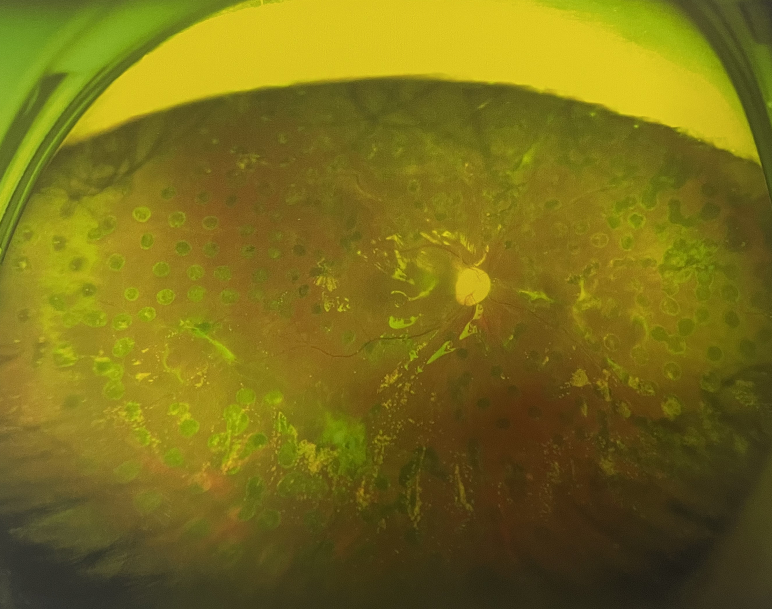

右眼術(shù)后

張小虎醫(yī)生為王女士進(jìn)行右眼玻璃體腔注藥術(shù),3天后進(jìn)行右眼23G玻璃體切割術(shù)后視力有所提升。

4個(gè)月后王女士來院取硅油,取油后視力恢復(fù)到0.6。“當(dāng)時(shí)來的時(shí)候真的只能看到模糊的影子,特別害怕覺得完了,想說眼睛估計(jì)要瞎了,沒想到手術(shù)后視力竟然提升了,現(xiàn)在也看得比較清楚了。”王女士說到。

張小虎醫(yī)生表示,糖網(wǎng)病進(jìn)展到嚴(yán)重增殖期帶來的視力損傷往往是極其嚴(yán)重的,目前王女士右眼從術(shù)前0.02恢復(fù)到術(shù)后0.6,已屬十分難得。